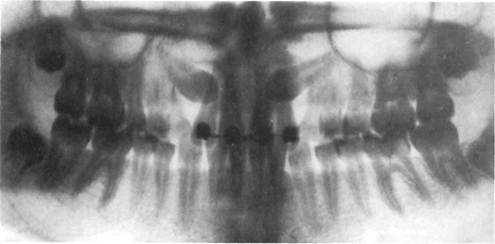

Рис. 13.26. Ортопантомограмма.

Ортопантомография, или панорамная томография, обеспечивает получение плоского изображения изогнутых поверхностей объемных областей. По ортопантомограммам (рис. 13.26) можно изучить степень

минерализации корней и коронок зубов, степень рассасывания корней молочных зубов и их соотношение с зачатками постоянных зубов, наклоны прорезавшихся и ретенирован-ных зубов по отношению к соседним зубам и срединной плоскости, зубо-альвеолярную высоту в переднем и боковых участках челюстей, резцового перекрытия, асимметрию правой и левой половин лица, средней и нижней части лицевогоскелета.